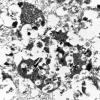

8I4 Granular Cell GBM (Case 8) EM 004 - Copy